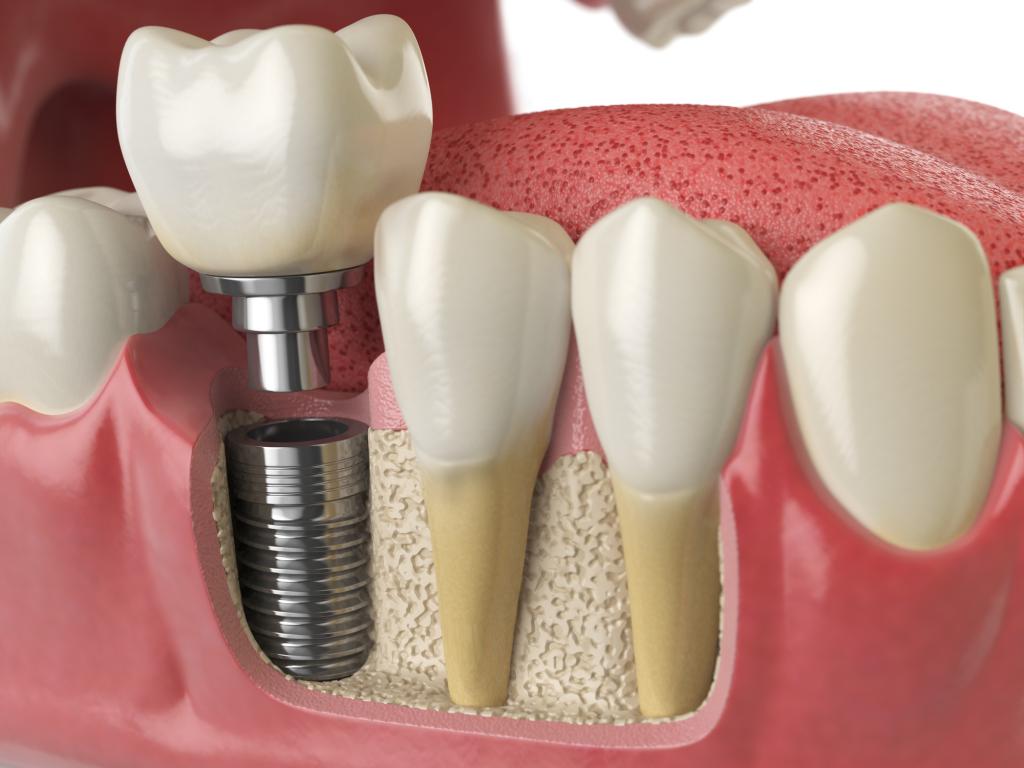

インプラントは、歯周病や虫歯で失った歯を人工的な歯の根となるインプラントを顎の骨に埋め込み、その上にセラミックなどで作られた人工の歯を装着する治療方法です。失った歯を自然な見た目で補うだけでなく、天然の歯に近い噛む力を回復させることもできます。また、インプラントは周囲の歯に負担をかけず、顎の骨を刺激して骨量を維持する助けとなるため、口腔の健康を保つのにも役立ちます。

インプラントの場合は顎の骨にチタンの人工歯根を埋め込んで人工の歯を取り付けるため、周囲の歯を削る必要がありません。インプラントはブリッジの治療法と比べて、残っている健康な歯に負担を与えないことが大きなメリットと言えます。

4インプラント体の埋入

6人工歯の装着

患者様のご希望の素材で製作した人工歯を取り付けます。かみ合わせを整えて調整された仮歯をもとに、精密に製作された人工歯をアバットメントに装着して、インプラント治療は終了です。